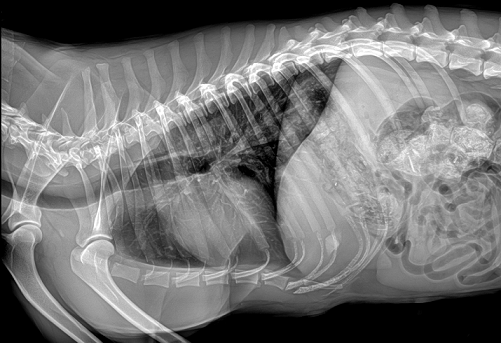

寵物DR是現(xiàn)在大多寵物醫(yī)院必備的醫(yī)療器械,它要比以往的X光更高科技一點(diǎn)兒:更清晰、易保存。寵物DR主要用于給寵物做X光檢查,在寵物不會(huì)說(shuō)話和不用做手術(shù)的情況下,檢查寵物身體內(nèi)是否有異物、骨折、炎癥和腫瘤等常見(jiàn)疾病。目前市面上好的寵物DR能令動(dòng)物影像成像迅速而清晰。可是應(yīng)該如何選擇寵物DR就成為了頭疼的問(wèn)題。

國(guó)產(chǎn)品牌普愛(ài)醫(yī)療寵物DR采用非晶硅平板探測(cè)器,可以令動(dòng)物影像成像清晰而快速,基本上5s左右就能使動(dòng)物影像清楚成像且無(wú)拖尾現(xiàn)象,而且分辨率高,極限空間分辨率可達(dá)到5.0Lp/mm;

普愛(ài)醫(yī)療寵物DR拍攝的高清照片

同時(shí),寵物影像成像尺寸較大,成像尺寸可達(dá)43cm x 43cm,并且以DICOM格式儲(chǔ)存數(shù)據(jù),極大的方便了醫(yī)療工作者們追蹤檢查時(shí)使用。同時(shí)還支持窗寬、窗位、放大、旋轉(zhuǎn)、正像和負(fù)像轉(zhuǎn)換等顯示功能。